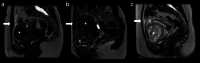

Results: Our first seventy patients showed significant symptom reduction and improvement of quality of life at 3, 6 and 12 months after MR-HIFU treatment compared to baseline. After the first 25 cases, a clear plateau phase was reached in terms of failed treatments. The median non-perfused volume percentage of these first 25 treatments was 44.6% (range: 0-99.7), compared to a median of 74.7% (range: 0-120.6) for the subsequent treatments.